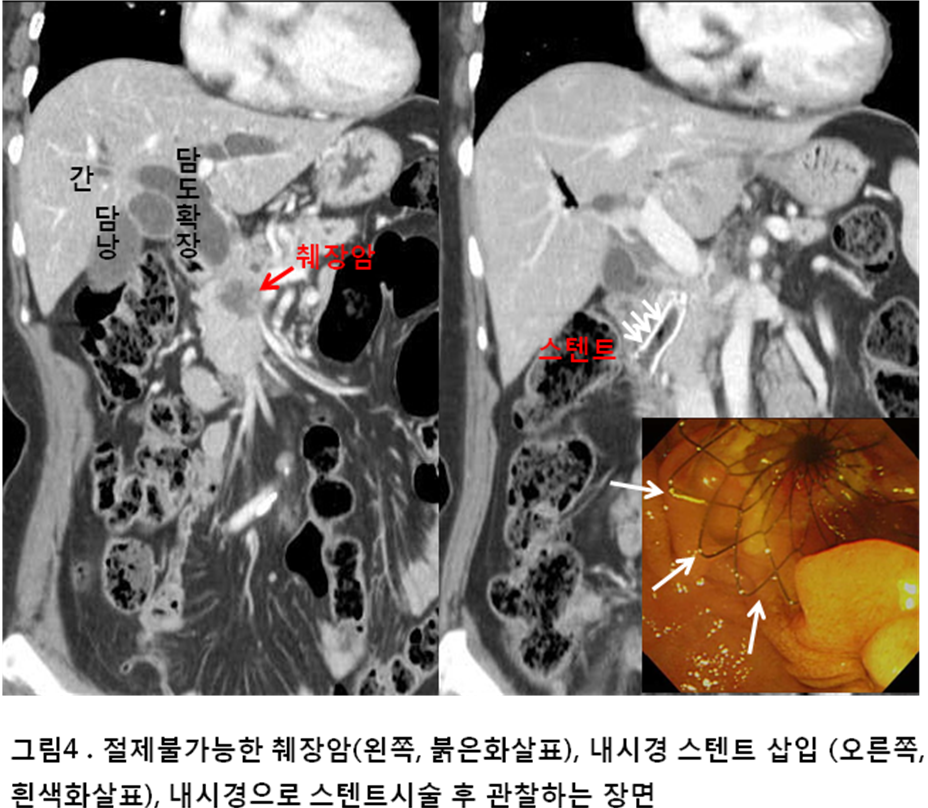

황달은 췌장암의 또 다른 심각한 증상으로, 체내의 빌리루빈 수치가 증가하게 되어 발생합니다. 이것은 췌장암이 췌장 내의 담관을 압박하거나 침범할 때 발생할 수 있습니다. 피부와 눈의 흰자위가 노랗게 변하는 증상은 반드시 주의해야 합니다.